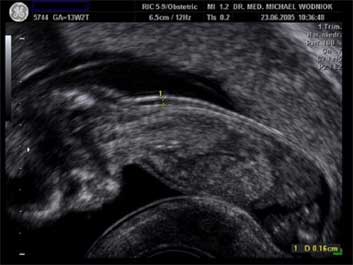

Die Nackenfalte stellt sich im Ultraschallbild im Bereich des hinteren Halses als ein dunkles Areal dar, welches auch bei fast allen gesunden Kindern in einer bestimmten Dicke (1-2 mm) zu sehen ist. Diese Nackenfalte ist normalerweise nur in der 11. bis 14. SSW darstellbar und verschwindet im weiteren Verlauf der Schwangerschaft.

Die Verdickung dieser Nackenfalte oder auch „nucheal tranlucency“ ( NT) genannt, die wir mittels einer speziellen Untersuchungstechnik in einem vorbestimmten Zeitfenster (11. - 14. SSW ) messen können, ist zunächst unspezifisch. Das heißt, dass sich bei einer Verdickung auch andere Erkrankungen wie Herzfehler, Skelettveränderungen und weitere Fehlbildungen verbergen können.